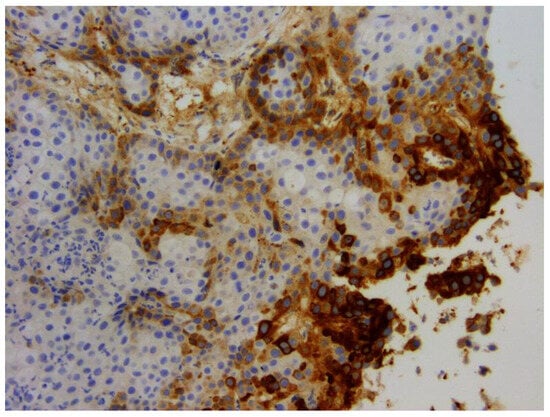

- Munday, J.S.; Gibson, I.; French, A.F. Papillomaviral DNA and increased p16CDKN2A protein are frequently present within feline cutaneous squamous cell carcinomas in ultraviolet-protected skin. Vet. Dermatol. 2011, 22, 360–366. [Google Scholar] [CrossRef]

- Thomson, N.A.; Munday, J.S.; Dittmer, K.E. Frequent detection of transcriptionally active Felis catus papillomavirus 2 in feline cutaneous squamous cell carcinomas. J. Gen. Virol. 2016, 97, 1189–1197. [Google Scholar] [CrossRef]

- Hoggard, N.; Munday, J.S.; Luff, J. Localization of Felis catus papillomavirus type 2 E6 and E7 RNA in feline cutaneous squamous cell carcinoma. Vet. Pathol. 2018, 55, 409–416. [Google Scholar] [CrossRef]